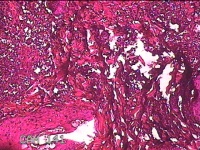

头部肿物

性别

男

年龄

18岁

临床诊断

头部局部肿物

一般病史

发现头顶部外凸结节半年余,近日出现局部破溃。

标本名称

大体所见

灰白暗红色肿物1.5x0.8x0.3cm一个,表面糜烂,结节表面有少许毛发,切开结节呈实性,切面灰白粉红色,质软。

图1